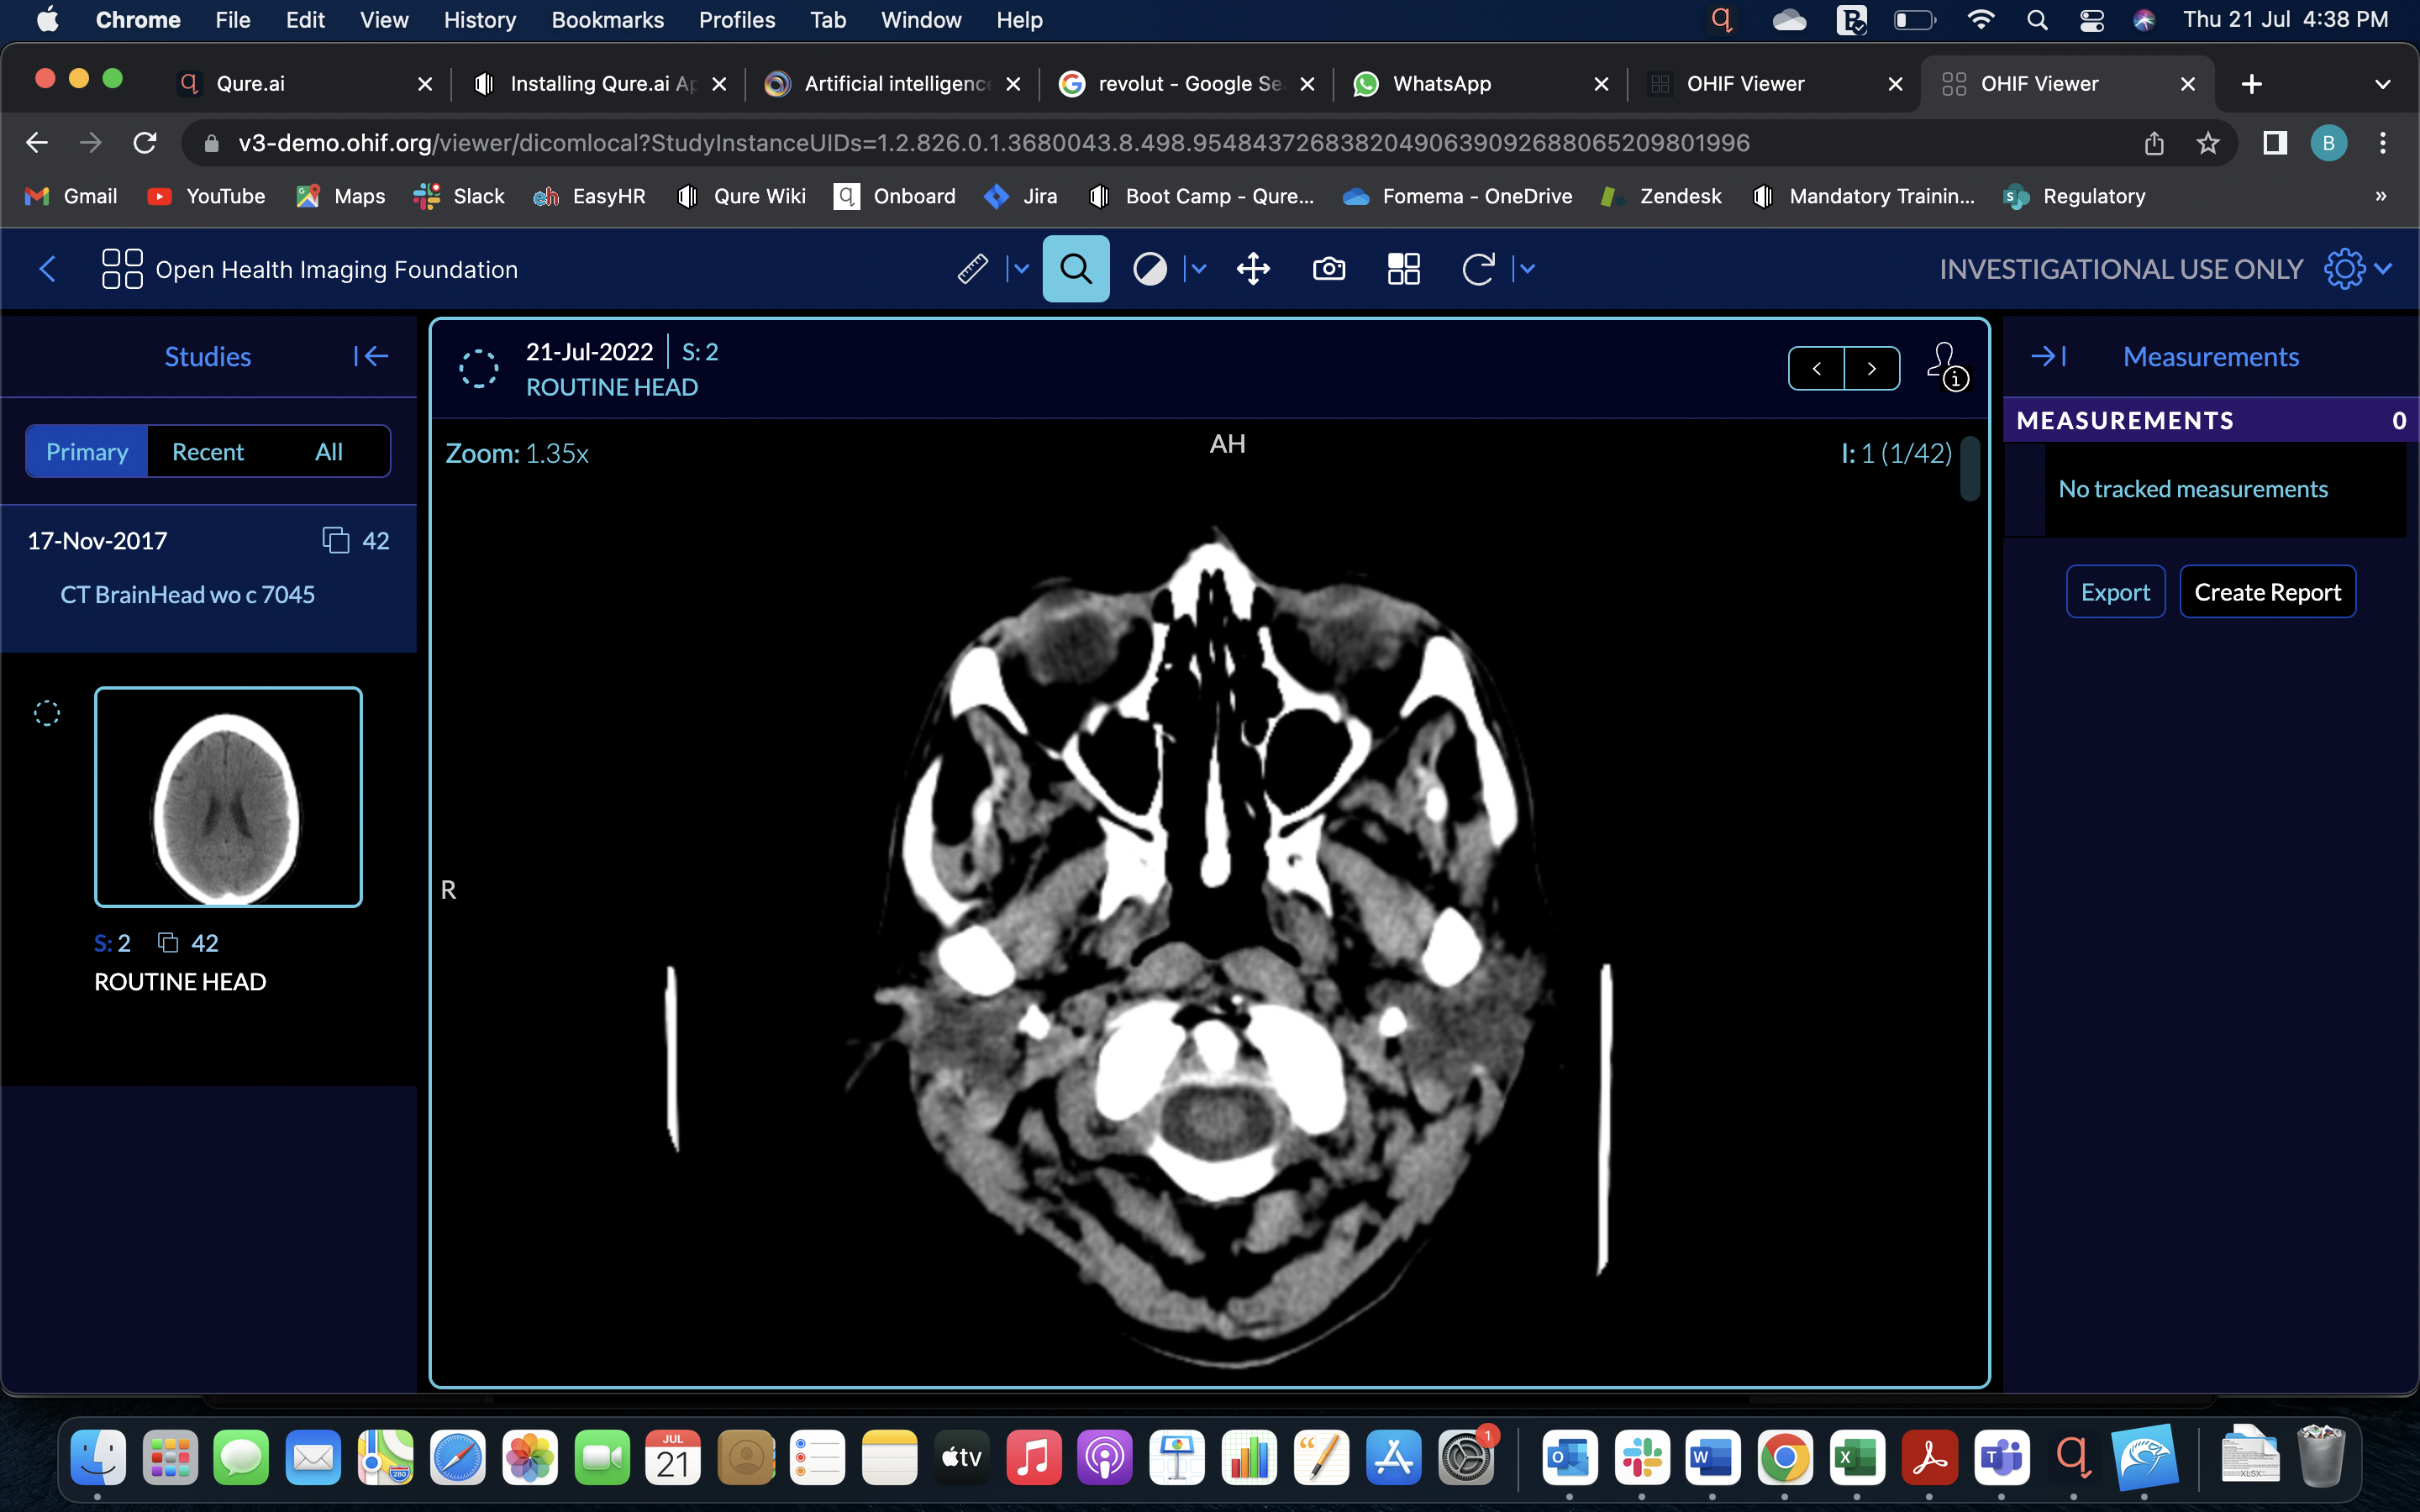

Image with same resolution appear to be sharper in Horos viewer compared OHIF

I have uploaded a head CT scan of the same resolution in Horos and OHIF viewer. The image in Horos viewer appear to be more sharper than OHIF. Any reason why this is happening?

I have attached the screenshots for both.

In local drag and drop in OHIF

OHIF through dicom web (orthanc)